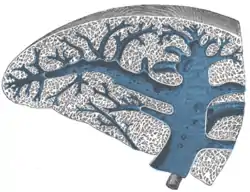

![]() Transverse section of the spleen, showing the trabecular tissue and the splenic vein and its tributaries | |

The fibroelastic coat of the spleen invests the organ, and at the hilum is reflected inward upon the vessels in the form of sheaths. From these sheaths, as well as from the inner surface of the fibroelastic coat, numerous small fibrous bands, the trabeculae of the spleen (or splenic trabeculae), emerge from all directions; these uniting, constitute the frame-work of the spleen.

The spleen therefore consists of a number of small spaces or areolae, formed by the trabeculae; in these areolae is contained the splenic pulp.